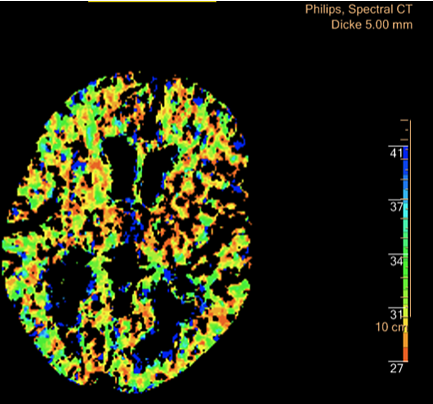

Ein Novum im Bereich der radiologischen Diagnostik stellt das Spektrale CT dar; das in Nordhausen installierte System gibt es in Deutschland bislang nur zweimal, das dritte kann nun von den Medizinern in Nordhausen genutzt werden. Wir können damit auf eine völlig neue Technologie zurückgreifen, die vor allem während der Therapie von Tumoren zum Einsatz kommen kann. So werden wir unter anderem ermitteln, wie viele Anteile des Tumors unter Behandlung absterben, wie viele Anteile noch durchblutet sind. Das Ziel hierbei ist, Chemotherapien zu optimieren und den Erfolg besser und genauer darstellen zu können.”, erläutert Prof. Malich.

Die Bildgebungsmöglichkeiten der neuen Technik eröffnen den Ärzten "neue Dimensionen" der Diagnose (Foto: Südharz-Klinikum)

Die Künstliche Intelligenz der eingesetzten Software ermöglicht sowohl die Herabsenkung der Röntgendosis als auch der Menge des eingesetzten Kontrastmittels. Deutlich verbessern wird sich im Südharz Klinikum die Bildgebung bei Schlaganfällen durch eine Darstellbarkeit der Durchblutung (Perfusion) des gesamten Hirns im CT sowie verbesserte Optionen der Abbildung von Gefäßen des Hirns.